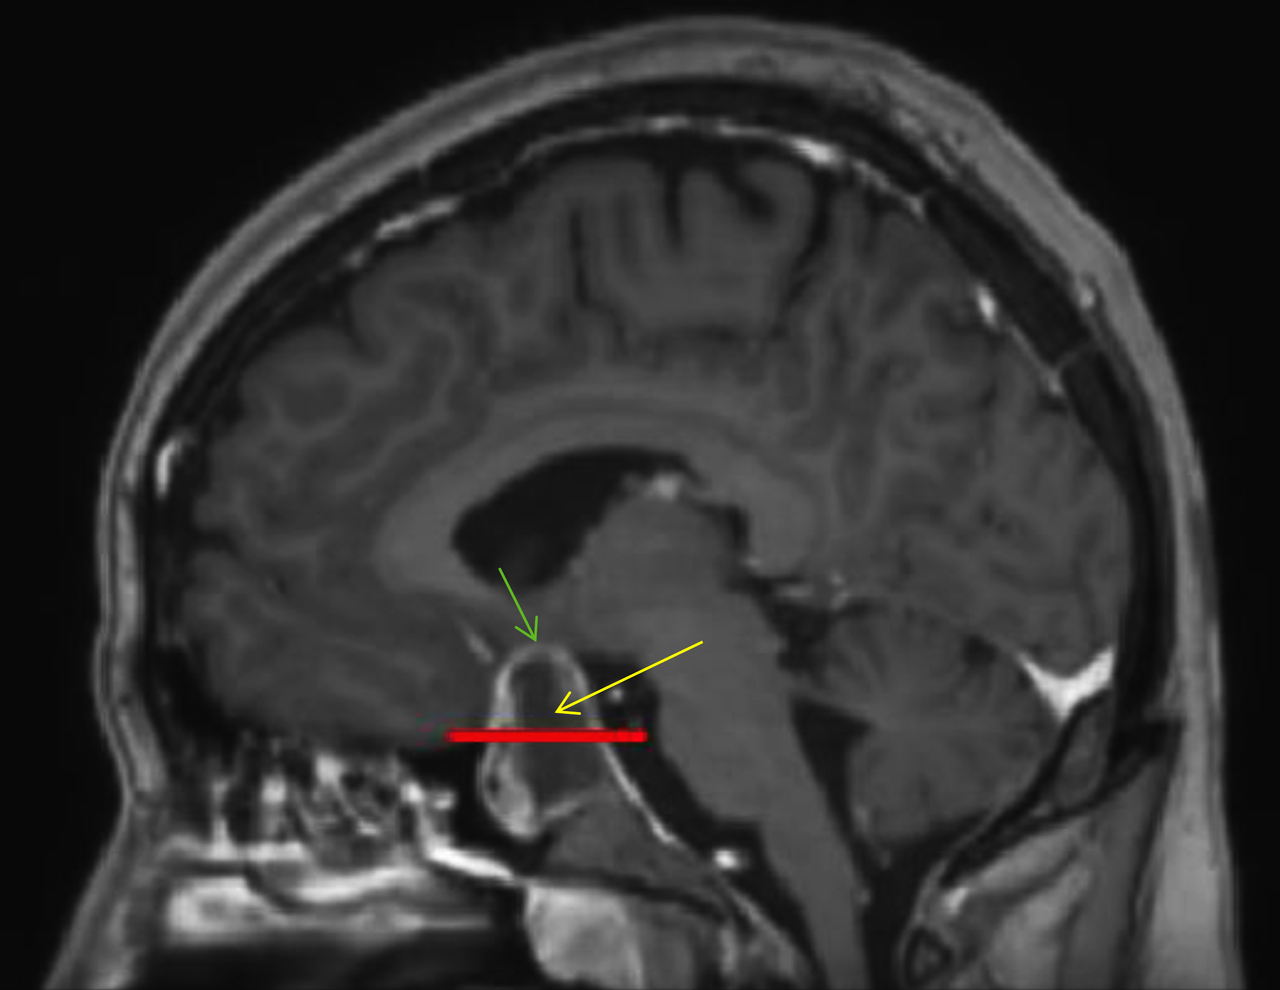

Le patient bénéficie également d’une imagerie par résonance magnétique (IRM) cérébrale devant un doute sur le scanner. Voici deux coupes (figures 2 et 3) :

Figure 2 (source : G. Kielwasser)

Sur la coupe coronale d’IRM en séquence T1 avec injection de gadolinium ci-dessous (figure 2 bis), on constate :

– sur l’image de gauche, que les sinus caverneux sont visibles de part et d’autre de la fosse pituitaire avec les vaisseaux rehaussés par le gadolinium. La flèche jaune pointe la masse hétérogène (centre hyposignal, périphérie hypersignal), en lien avec l’apoplexie pituitaire qui correspond à une hémorragie au sein du macro-adénome hypophysaire ;

– sur l’image de droite, que la ligne rouge correspond à une limite approximative de la loge pituitaire que l’hypophyse ne devrait pas dépasser. La flèche verte pointe le chiasma optique comprimé par la masse.